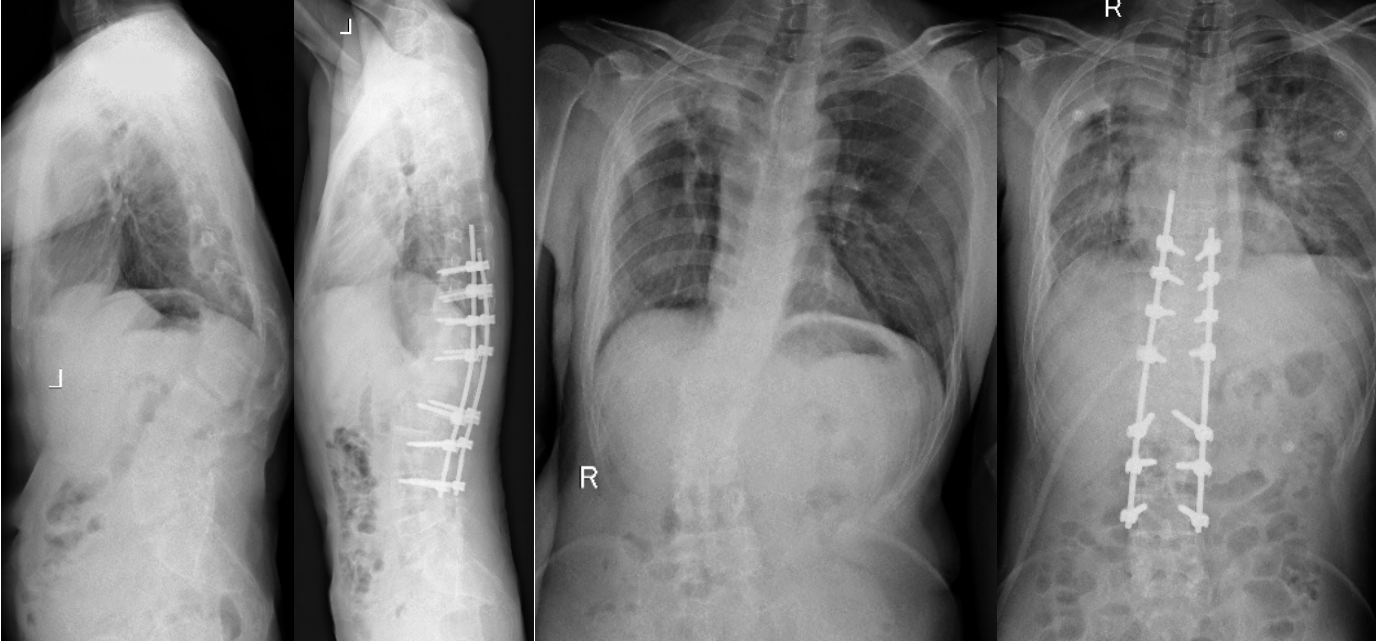

病例分享:脊柱后凸畸形矫形术

图片尺寸1014x635